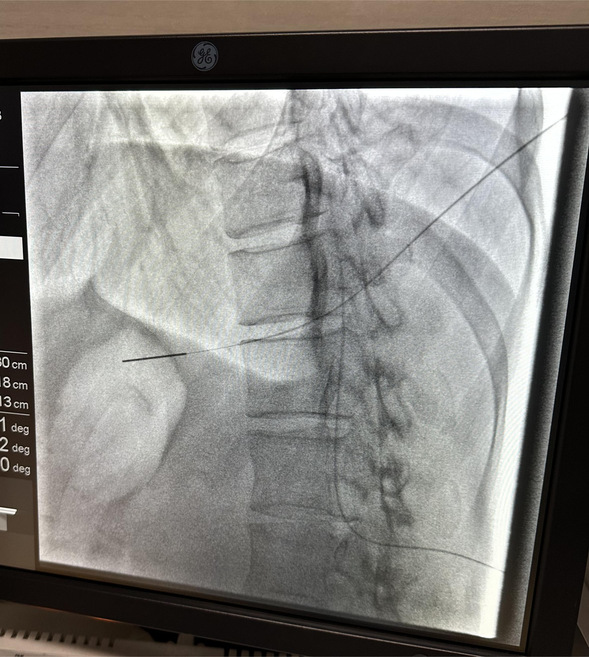

疼痛科医生王鑫凯、丛威亮为患者行鞘内输注系统植入术

根据病情,王鑫凯医生为宋阿姨制定了行“鞘内输注系统植入术”的手术方案进行疼痛治疗。完善的术前检查后,在局部麻醉下进行了手术治疗,手术过程顺利。术后,宋阿姨疼痛缓解明显,对于生活中偶尔出现的“爆发痛”,也可以通过快速给药的方式进行治疗。